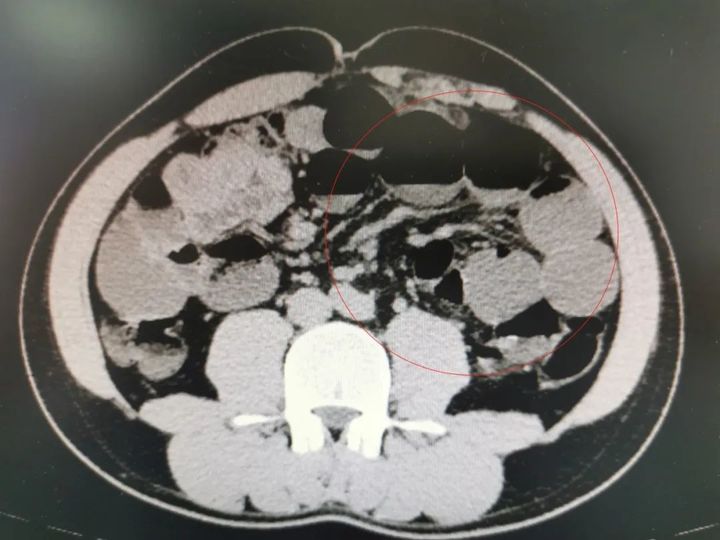

小汪小肠梗阻影像图